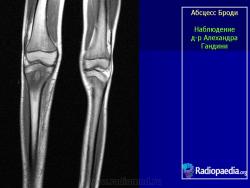

Рентгенологически обнаруживают полость с чёткими склерозированными контурами, при обострении периостальные наслоения, остеосклероз.

Особенностью гнойника Броди является локализация в губчатом костном веществе, причем практически почти никогда не поражаются мелкие или плоские кости, а исключительно большие трубчатые кости, а именно метафизарные концы. На первом месте по частоте заболевания стоят суставные концы костей, образующих коленный, голеностопный и локтевой суставы. Самым типичным и излюбленным местом локализации гнойника является большеберцовая кость, на долю которой выпадает 80% всех случаев, причем проксимальный метафиз поражается чаще, чем дистальный. Гнойник предпочтительно располагается поверхностно, под корковым слоем кости.

Из клинических особенностей абсцесса Броди наиболее характерными являются чрезвычайно длительное течение — до двух и трех десятилетий, боли в кости, обычно усиливающиеся по ночам и после движения или упражнения, а также временное припухание мягких тканей. Мужчины во много раз чаще заболевают, чем женщины. Заболевание начинается в большинстве случаев остро, но может иметь и первично-хроническое течение. Ввиду близости гнойника к суставу во многих случаях на первый план выступают суставные явления, которые настолько доминируют во всей картине заболевания, что мысль о первичном заболевании кости и не приходит в голову ни больному, ни врачу. Эти экссудативные синовиты, или, как их принято называть, содружественные, „симпатические воспаления суставов”, имеют перемежающееся течение. Иногда на протяжении длительных периодов в несколько лет все симптомы совершенно затихают, чтобы вдруг вновь появиться. Температура остается нормальной, картина крови не меняется заметным образом.

Рентгенологическое исследование имеет решающее диагностическое значение. Все детали патологоанатомической картины абсцесса Броди передаются в точности и на рентгеновских снимках (рис. 207 и 208). Изолированная, правильной округлой формы полость, без секвестра, с резко ограниченными гладкими внутренними контурами, расположенная среди склерозированного губчатого вещества, на типичном месте — в метафизарном конце большой трубчатой кости, слегка утолщенной благодаря периостальным наслоениям, — эта рентгенологическая картина при поддержке клинических симптомов разрешает диагностическую задачу. При этом следует учесть, что между, так сказать, классическим типичным абсцессом Броди и другими формами хронического остеомиелита бывают и переходные формы — и по местоположению, размерам, форме, характеру реактивных изменений в окружности, секвестрации и т. д. Это ведь в природе вещей: классификация показывает всегда несколько условно типичное, жизнь преподносит многообразие, не укладывающееся в строгую жесткую схему. Никоим образом не следует злоупотреблять диагнозом абсцесса Броди и ставить его расширительно, чуть ли не во всех случаях более или менее ясно выраженной полости при обычном хроническом остеомиелите: абсцесс Броди — это совершенно определенное клинико-рентгено-анатомическое понятие, это четкая нозологическая единица, и диагноз оправдан лишь в тех случаях, когда рентгенологическая картина удовлетворяет всем вышеперечисленным критериям.